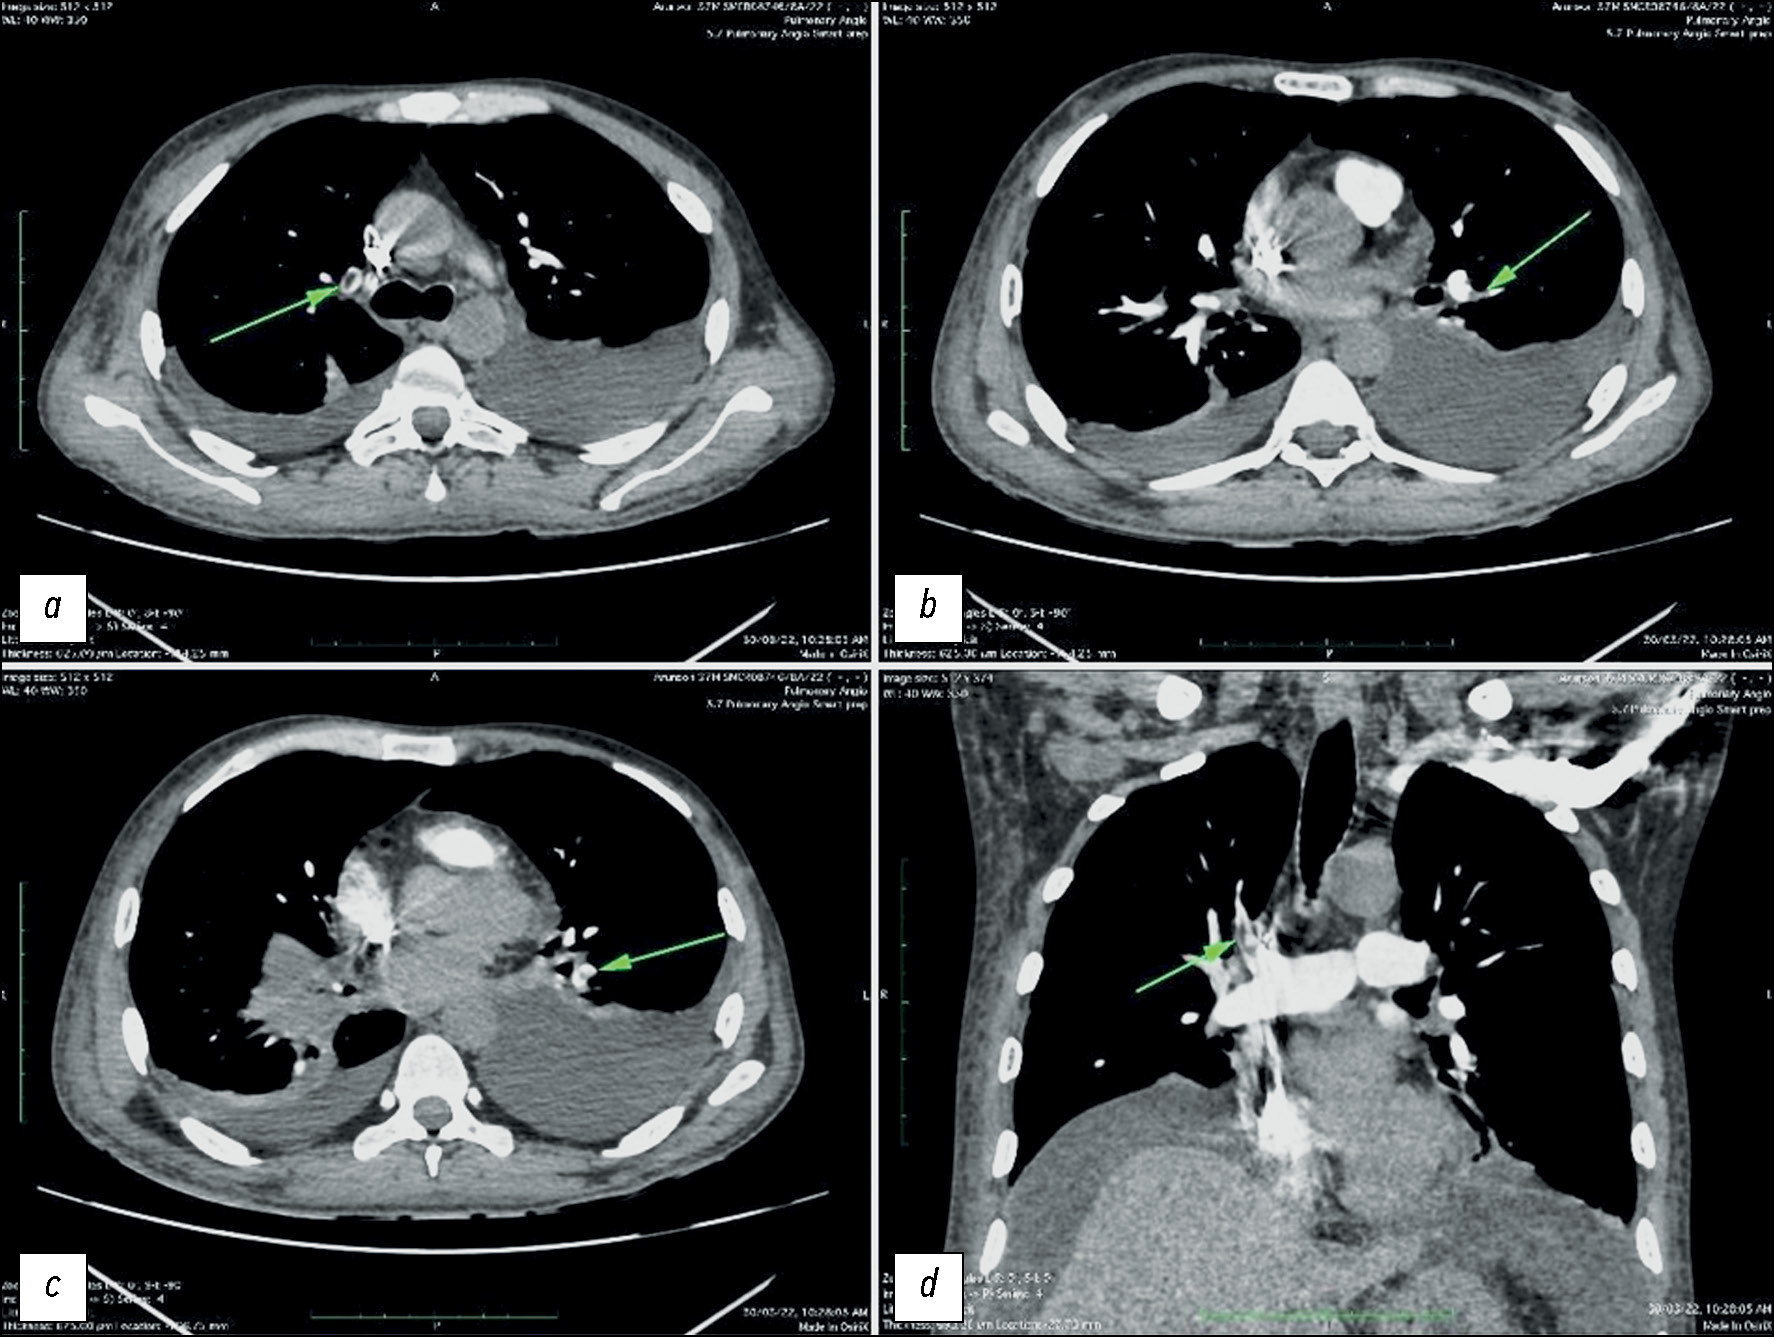

结果。研究中,11 名患者出现肺栓塞,7 名患者的肠道血管出现明显变化,包括肠壁增厚、肠系膜缺血和网膜梗死,这表明 COVID-19患者胃肠道血管潜在的损伤。研究发现,COVID-19的存在与肺栓塞的发生呈正相关性,肺栓塞平均在发病11天后确诊。根据肺血管计算机断层扫描,在24名COVID-19严重急性呼吸道病程的患者中,有7人发现了肺栓塞。此外,在10名接受人工通气的患者中,有7人出现了这种并发症。在7名肠道血管发生变化的患者中,有4人也发现了肺栓塞,这表明这些变化之间存在着显著的关系。观察到的肠道血管变化是由于血管内血栓形成所致。

结论。根据结果可以得知,严重的COVID-19患者往往同时伴有肺栓塞,而且肠道血管也会发生变化。此外,多变量分析显示,有创人工通气与肺栓塞的发生存在关联。因此,这些患者的治疗决策应基于增强计算机断层扫描,因为不使用造影剂的标准计算机断层扫描无法提供必要的信息。